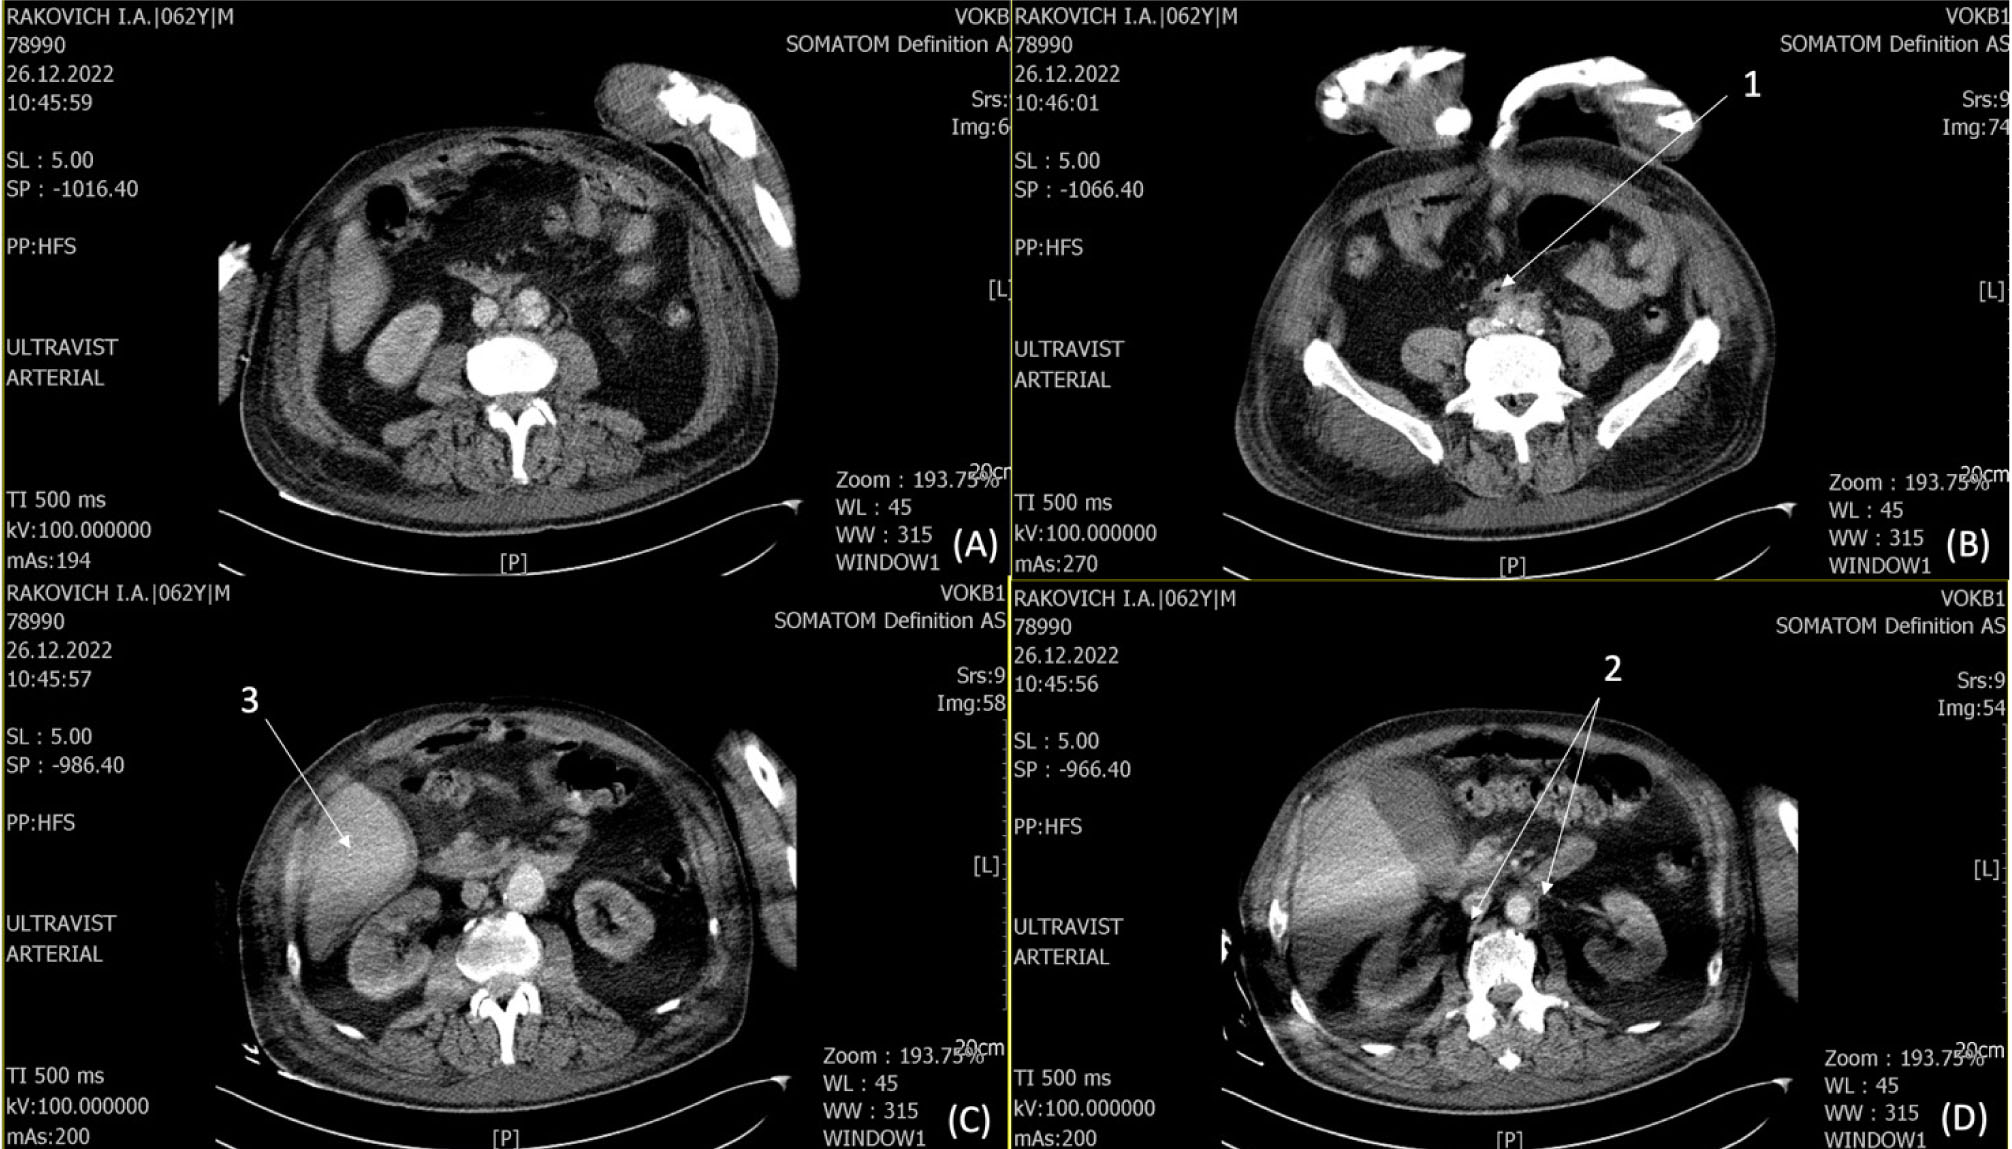

Пациент в возрасте 60 лет в 2016 г. после резекции аневризмы инфраренального отдела аорты с внутримешковым аорто-подвздошным протезированием справа, аорто-бедренным протезированием слева в другом лечебном учреждении. Поступил в нашу клинику в сентябре 2021 года с жалобами на наличие пульсирующего мешотчатого образования в области верхней трети правого бедра, подъем температуры до 37,5–40,1 °С в течение двух недель. Операции в анамнезе: вскрытие абсцесса правой голени от июля 2020 г., вскрытие абсцесса и флегмоны правой нижней конечности от января 2021 г., холецистэктомия от января 2021 г. Операции выполнялись в других лечебных учреждениях. Выполнено ультразвуковое исследование (УЗИ) мягких тканей правого бедра: в верхней трети и средней трети по внутренней поверхности бедра вдоль сосудистого пучка визуализируется гипоэхогенное образование неоднородной структуры на протяжении более 10 см толщиной от 0,6 до 1,2 см на глубине до 1,4 см аваскулярное при цветном дуплексном сканировании (ЦДК). В верхней трети бедра визуализируется шаровидной формы аневризма с d – 4,6 на протяжении 5,1 см. Инфильтрация окружающих тканей. Обращаем внимание: у пациента уже в анамнезе два глубоких гнойных очага не ясного происхождения в правой нижней конечности. На КТ ангиографии брюшной аорты и подвздошных сосудов – псевдоаневризма с формирующимся абсцессом (рис. 2).

Рис. 2. КТА брюшной аорты и подвздошных сосудов – картина, характерная для ложной аневризмы с деструктивными воспалительными изменениями окружающей клетчатки (формирующийся абсцесс) (C). Не исключается парааортальный воспалительный процесс на уровне бифуркации за счет пакета увеличенных лимфатических узлов (A, B, D). Субокклюзия глубокой и поверхностной бедренных артерий справа